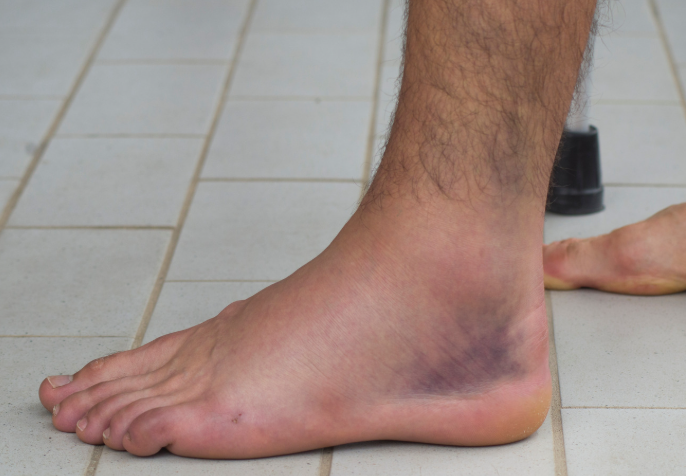

Do I Need an MRI or X-Ray?

Not always. Most ankle instability can be diagnosed clinically during physiotherapy assessment. Imaging is only recommended if:

- There is severe swelling or bruising

- Pain persists longer than expected

- There is suspicion of fracture or significant tearing

- You’re not responding to treatment